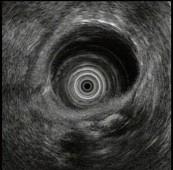

问题 男性,44岁反复上腹钝痛2年余伴纳差,超声内镜如图,胰腺病变可能的诊断是 ( )

选项 A.正常 B.胰腺囊肿 C.慢性胰腺炎 D.胰腺囊腺癌 E.胆总管结石伴扩张

答案 C